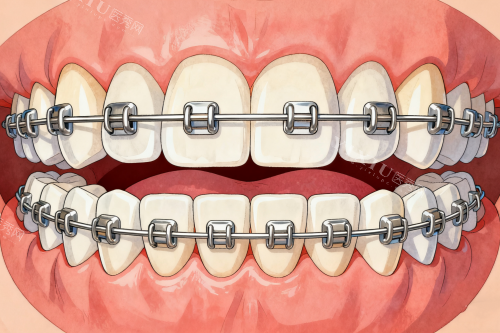

终于轮到我了,我跟着导医小姐姐来到了医生的诊室。给我看诊的是一位姓王的医生,王医生特别和蔼可亲,他先让我躺在治疗椅上,然后开始给我检查牙齿。他一边检查,一边跟我讲解我的牙齿情况,说得特别详细,什么牙齿排列不整齐、咬合关系不正常之类的,我虽然不太懂,但也能大概明白我的牙齿问题挺重的的。检查完之后,王医生根据我的牙齿情况,给我制定了好几种矫正方案,有传统的金属托槽矫正,还有隐形矫正。他耐心地给我分析了每种方案的优缺点,还结合我的个人需求和经济情况,推荐我做隐形矫正。他说隐形矫正美观度高,几乎看不出来戴了矫正器,而且对日常生活的影响比较小。我听了王医生的介绍,觉得隐形矫正挺适合我的,就决定采用这个方案。

过了几天,我接到了郑州马泷齿科的电话,说矫正方案已经确定好了,让我过去试戴矫正器。我迫不及待地赶到了诊所。见到王医生后,他又跟我详细地讲了一下矫正方案的细节,还教我怎么佩戴和摘取矫正器,以及矫正期间的注意事项。我戴上矫正器之后,感觉还挺舒服的,没有那种特别紧勒的感觉。王医生仔细地检查了矫正器的佩戴情况,调整了一下,确保矫正器和我的牙齿贴合得很不错。

从那之后,我就开始了漫长的牙齿矫正过程。每隔一段时间,我就要去郑州马泷齿科复诊一次。每次复诊,王医生都会认真地检查我的牙齿矫正情况,根据牙齿的移动情况调整矫正器。他还会跟我聊聊我的日常生活,问问我戴矫正器有没有什么不舒服的地方,让我感觉特别温暖。护士小姐姐们也会在旁边提醒我一些注意事项,比如要按时刷牙、保持口腔清洁、避免吃太硬的食物等等。